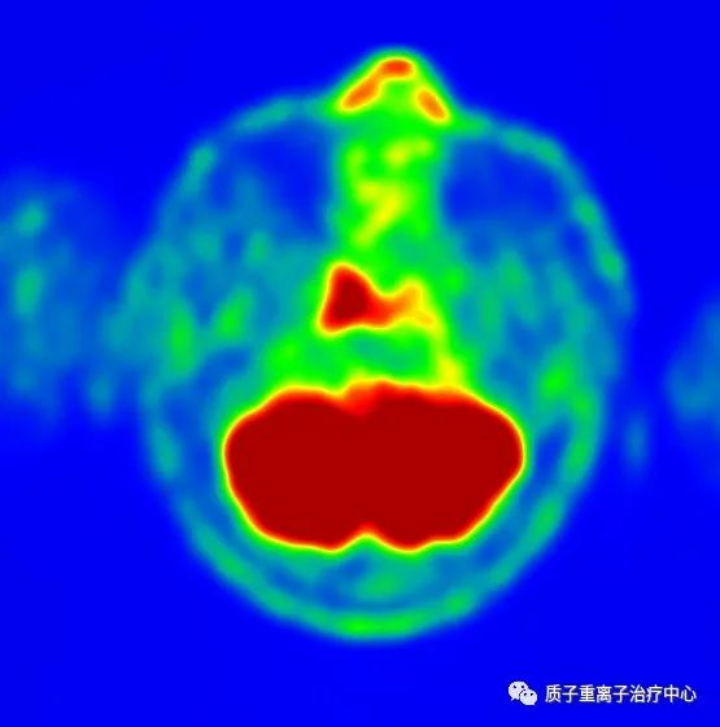

鼻咽癌质子治疗35个月,复查结果显示痊愈时间:2024-04-09 鼻咽癌质子治疗35个月,复查结果显示痊愈鼻咽癌是指发生于鼻咽腔顶部和侧壁的恶性肿瘤。是我国高发恶性肿瘤之一,尤其在华南地区和广东省,所以鼻咽癌在我国又被称为“广东瘤”,发病率为耳鼻咽喉恶性肿瘤之首,男性发病率为女性的2~3倍,40~50岁为高发年龄组。常见临床症状为鼻塞、涕中带血、耳闷堵感、听力下降、复视及头痛等。鼻咽癌大多对放射治疗具有中度敏感性,放射治疗是鼻咽癌的首选治疗方法。但是对较高分化癌,病程较晚以及放疗后复发的病例,手术切除和化学药物治疗亦属于不可缺少的手段。 患者病例 患者男,44岁 于2019年3月余前无意间发现左颈部肿块,质韧,活动度可,无压痛及触痛,最大径约2cm,后进行性增大于2019-09-17到南方某医院在表面麻醉下行纤维鼻咽喉镜检查取活检,病理结果回示:(鼻咽部)非角化性分化型癌。免疫组化结果:CK-Pan(++)EBER(原位杂交)(+++),Ki67(30%+),P40(++),EGFR(90%+,染度:强)。2019-09-19行鼻咽与颈部淋巴结MR示:鼻咽右侧壁及顶后壁稍增厚:鼻咽癌?伴双侧颈部增大淋巴结,未行相关治疗出院。 经多方会诊,慎重选择,文献资料证实质子治疗是目前最为先进成熟的放射治疗方式,与X射线放射治疗相比较,可明显提高疗效,明显保护腮腺、颞颌关节、上腭、口腔等重要组织结构。淄博万杰肿瘤医院质子治疗中心2004年治疗第一例病人,是国内最早开始质子放射治疗的医院,在治疗鼻咽癌方面有着丰富的治疗经验。患者为寻求质子治疗来我院,经院质子治疗专家组会诊,可行质子治疗。 质子治疗前CT和PET图像 (2019年10月)

2021年10月复查PETCT报告显示:未见明显肿瘤征象